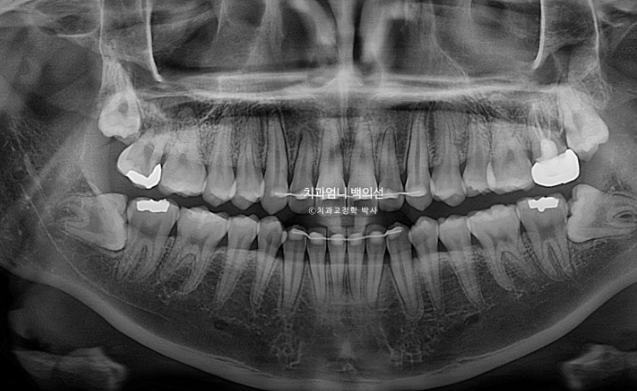

23년 12월 앞니 부분교정을 위해 오신 분입니다.

앞니 두 개가 크기도 하고 내려와 있습니다.

파란 화살표에 작은 어금니 덧니도 보입니다.

아래 앞니가 많이 삐뚭니다.

어금니 교합이 그리 좋은 편은 아니지만 환자분은 씹는데 불편함을 못 느끼는 상태였고 앞니 배열만 원하셨습니다.

기간과 비용, 환자분의 상황 등 모든 것을 고려해서 일부 포기하고 앞니 부분교정에 들어갔습니다

나중에 언젠간 환자분이 시간이 되고 여유가 될 때 전체교정을 다시 하기로 했습니다.

24.09

부분교정인만큼 치근흡수는 없고 뿌리 평행도도 양호합니다.